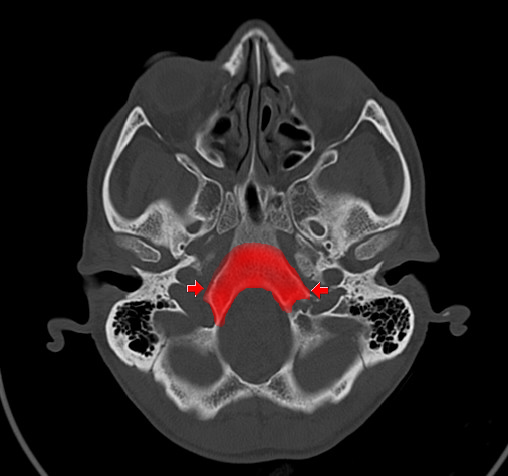

Während das Erkrankungsalter bei sakralen Chordomen typischerweise im 6. Lebensjahrzehnt liegt, werden Schädelbasis-Chordome durchschnittlich um das 38. Lebensjahr diagnostiziert [9,10]. Bei den Schädelbasis-Chordomen sind beide Geschlechter gleich betroffen.